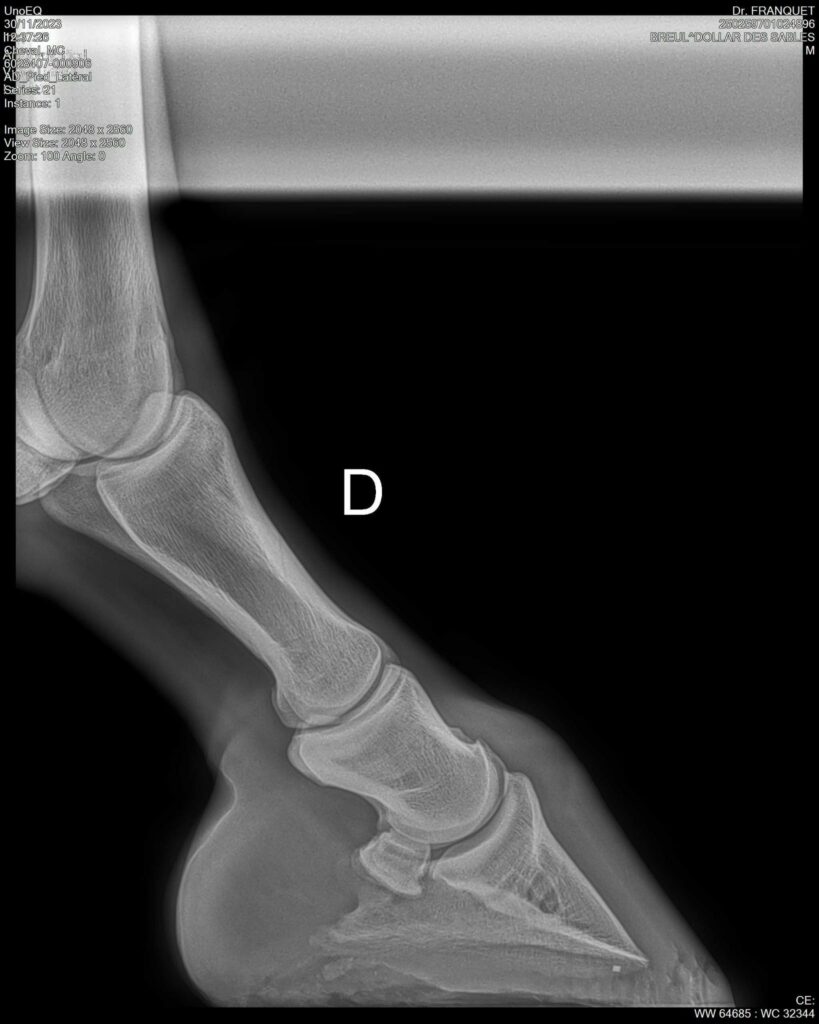

DOLLAR DES SABLES, Selle Français, hongre, 12 ans par DOLLAR DE MURIER x ABKE (ACORADO). Classé 135 avec professionnel à fait 125 avec amateur, récemment classé sur amateur 1GP 120. Très beau modèle ! Gentil cheval, respectueux avec des moyens et du sang. Transport OK, maréchalerie OK, santé RAS, Bilan clichés radios OK.

RADIOS